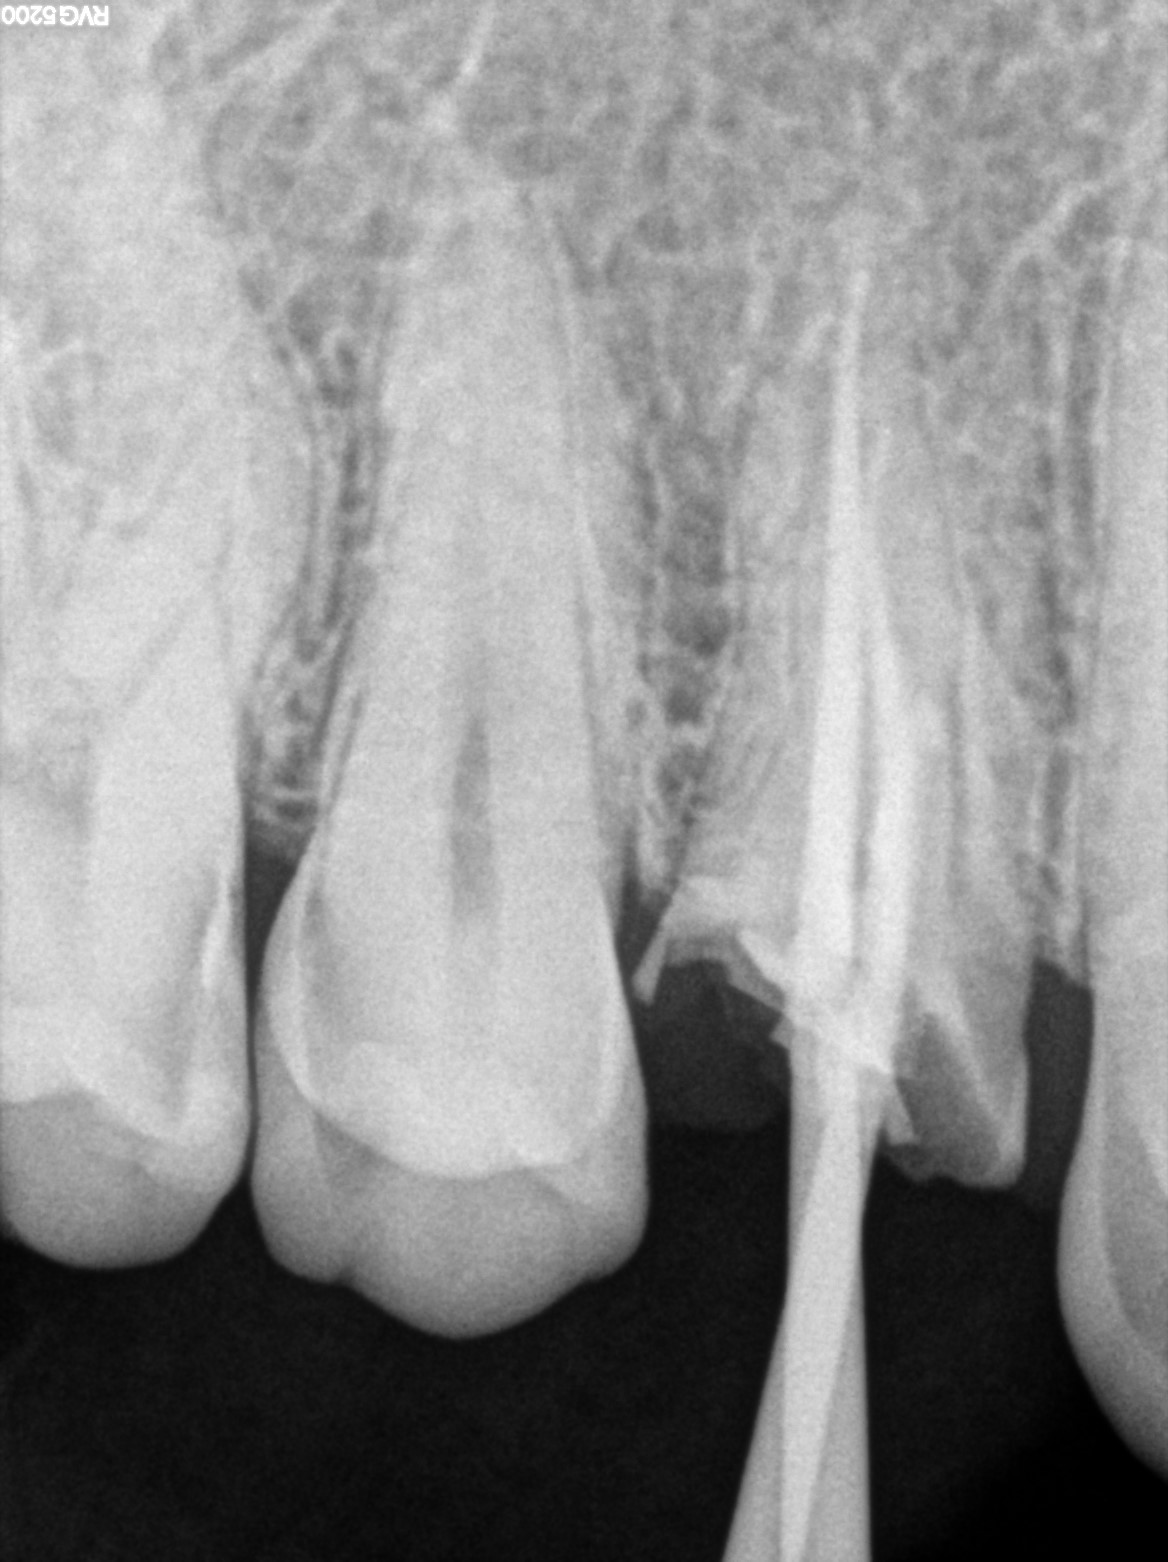

Dental Radiographs FHIR: DocumentReference · LOINC 24641-7

R55.jpg

24641-7